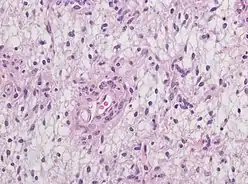

Neuropathology

Neuropathology is a specialty within the study of pathology focused on the disease of the brain, spinal cord, and neural tissue.[33] This includes the central nervous system and the peripheral nervous system. Tissue analysis comes from either surgical biopsies or post mortem autopsies. Common tissue samples include muscle fibers and nervous tissue.[34] Common applications of neuropathology include studying samples of tissue in patients who have Parkinson's disease, Alzheimer's disease, dementia, Huntington's disease, amyotrophic lateral sclerosis, mitochondria disease, and any disorder that has neural deterioration in the brain or spinal cord.[35][36]